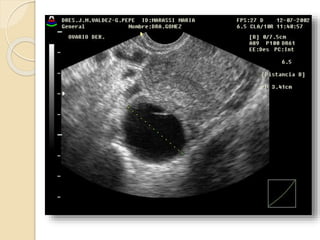

Quistes Funcionales

Quistes foliculares:

Resultan de una falla en la involución.

El folículo se distiende y mide mas de

30mm de diámetro. No dan síntoma a

menos que adquieran mucho tamaño y

sufran ruptura, torsión o hemorragia

Quistes Funcionales Quistesfoliculares: Resultan de una falla en la involución. El folículo se distiende y mide mas de 30mm de diámetro. No dan síntoma a menos que adquieran mucho tamaño y sufran ruptura, torsión o hemorragia